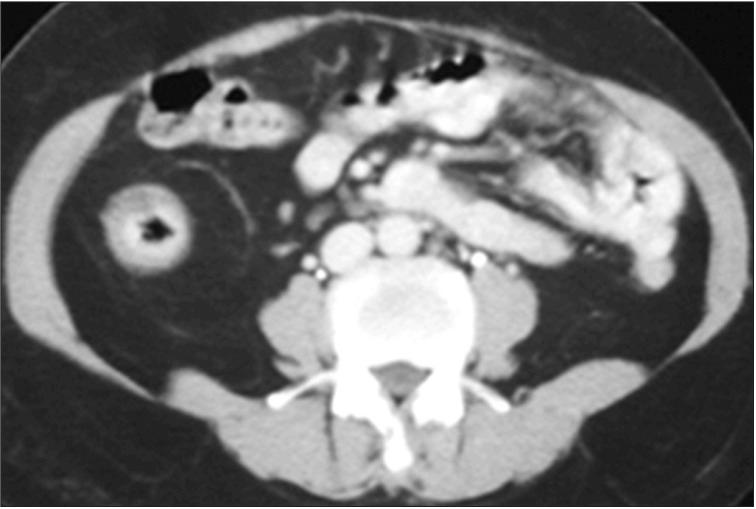

Since Taiwan is an endemic area for tuberculosis (TB), differential diagnosis between the intestinal TB and Crohn's disease is an important issue. The steering committee of Taiwan Society of Inflammatory Bowel Disease (TSIBD) has arranged a seminar accordingly on May 24th, 2014 and the different point of views by gastroenterologist, radiologist, pathologist and infectious disease specialist were suggested to help the proper diagnosis and management of these two diseases.

由于台湾是结核病的流行地区,肠结核与克罗恩病的鉴别诊断是一个重要问题。台湾炎症性肠病学会(TSIBD)指导委员会于2014年5月24日相应地安排了一次研讨会,并提出了胃肠病学家、放射科医生、病理学家和传染病专家的不同观点,以帮助对这两种疾病进行正确的诊断和管理。